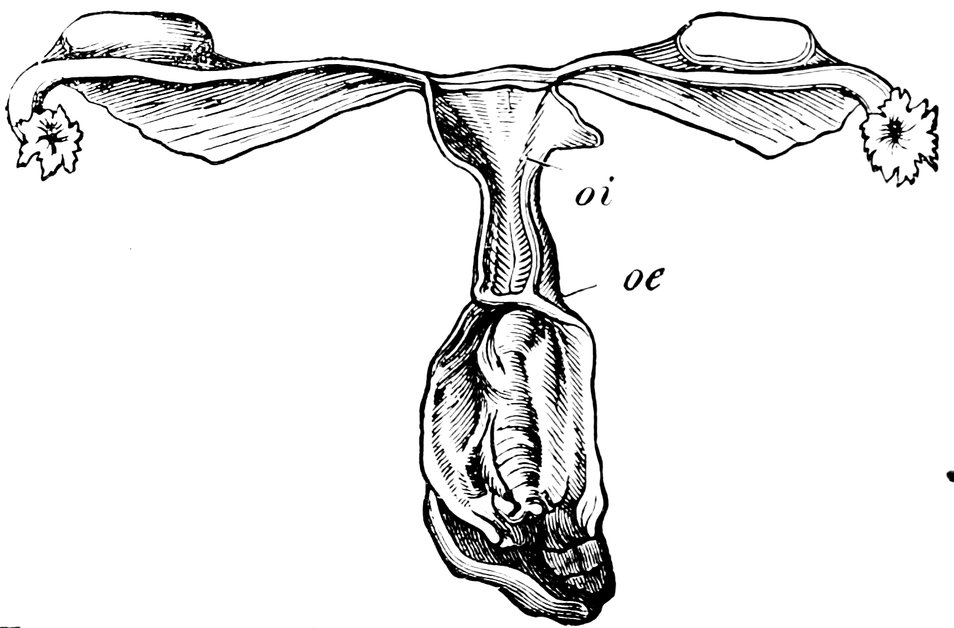

| 50. | The uterus, the left Fallopian tube and the left ovary, etc | 207 |

| 70. | Congenital Atrophy of the Uterus (after Virchow), oi, Ostium internum; oe, Ostium externum | 500 |